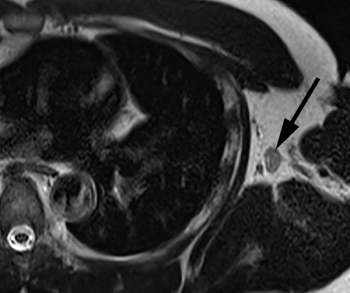

Emerging research suggests that the contrast-enhanced, in-phase Dixon sequence may be the most optimal sequence for detecting biopsy clips on breast magnetic resonance imaging (MRI).